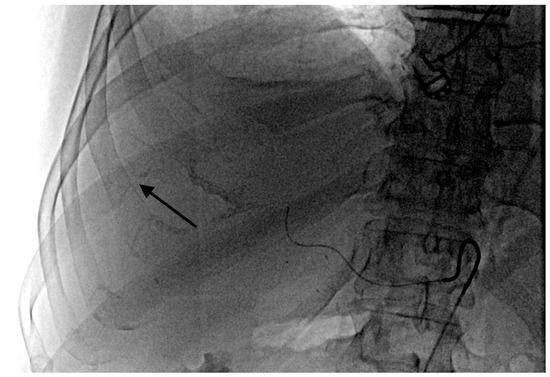

- Grade 4 stasis. Embolizate contrast in segmental vessels (Figure 4).